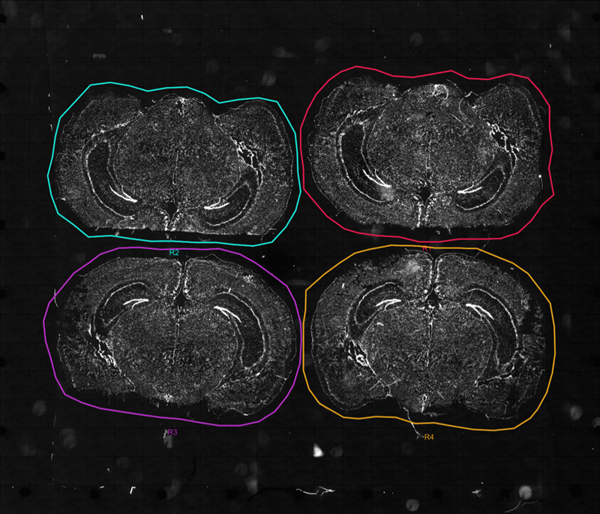

ͬһ��slide��ͬ�r�N4��С���X�M����Ƭ